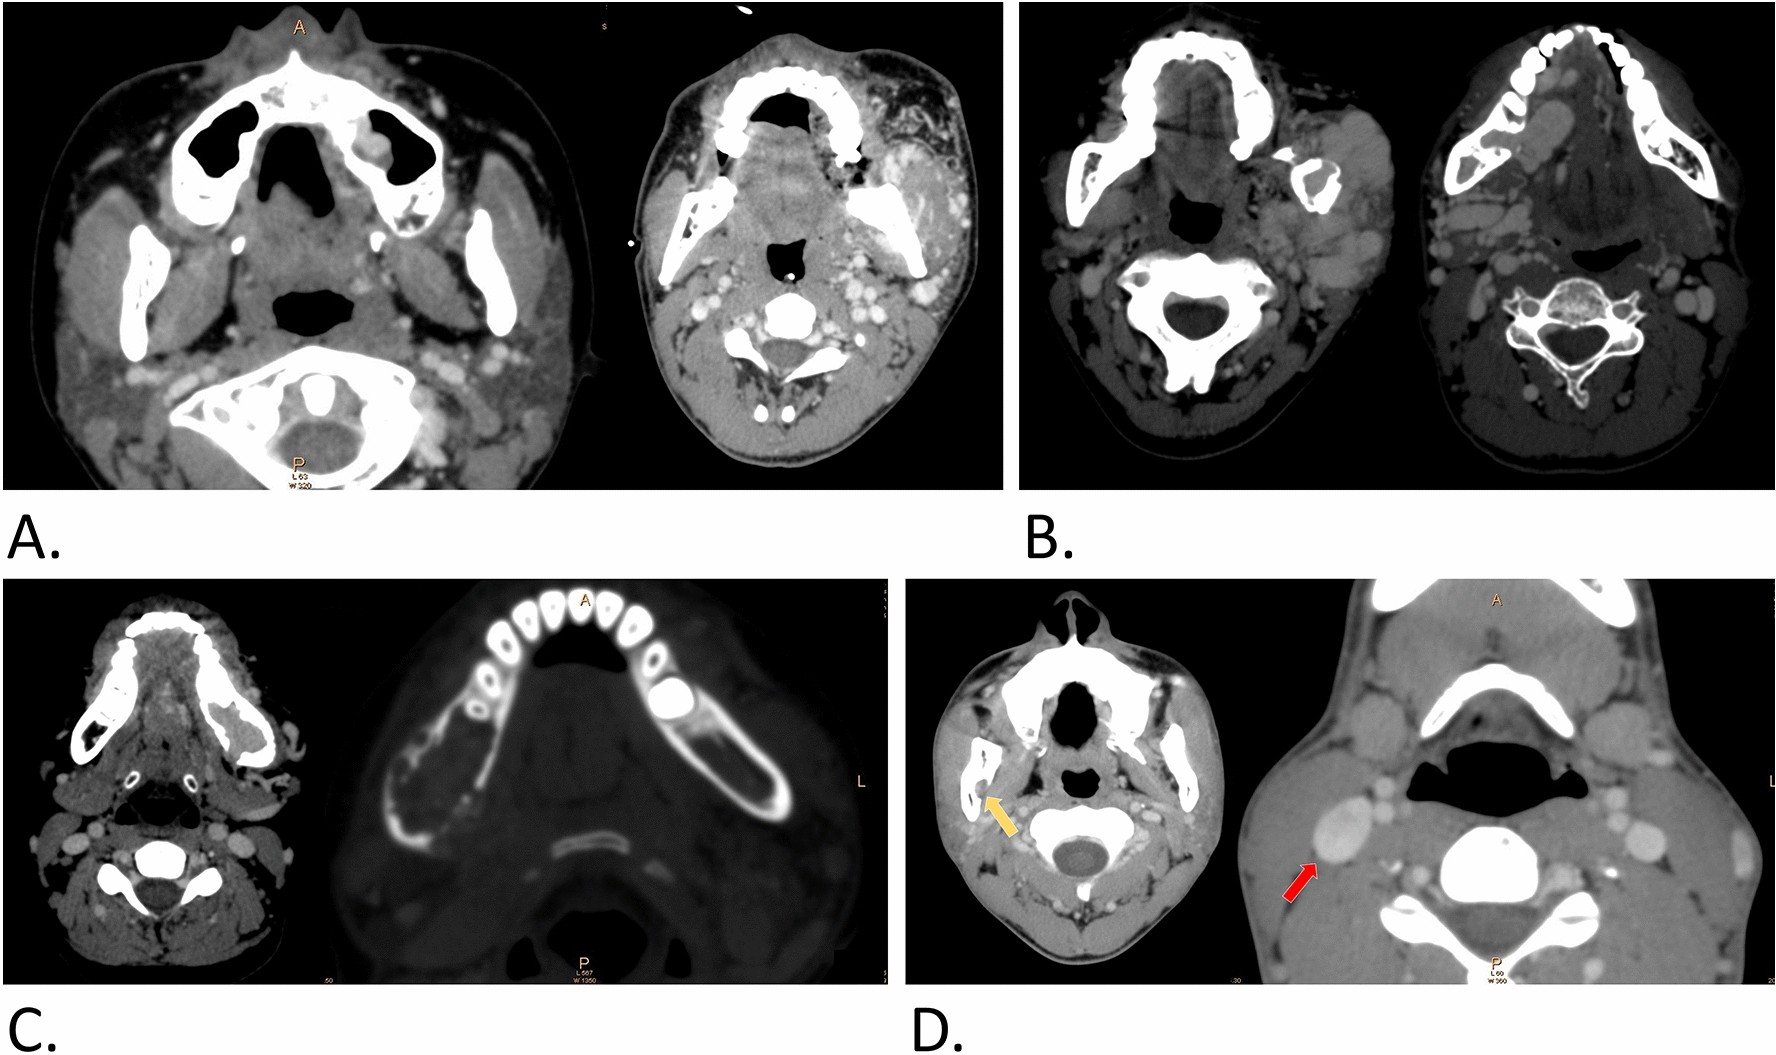

Figure 4

Other manifestations on contrast-enhanced CT of j-AVMs. (a) Involvement of the adjacent maxillary sinus and soft tissue. (b) Enlarged and tortuous draining veins showing abnormal arterial enhancement located inside or adjacent to either side of the jaw. (c) Signs of penetration of large vessels breaking through normally structured cortical bone. (d) Enlarged and wider mandibular foramen (yellow arrow) and enlarged external jugular vein (red arrow) compared with those on the contralateral side.